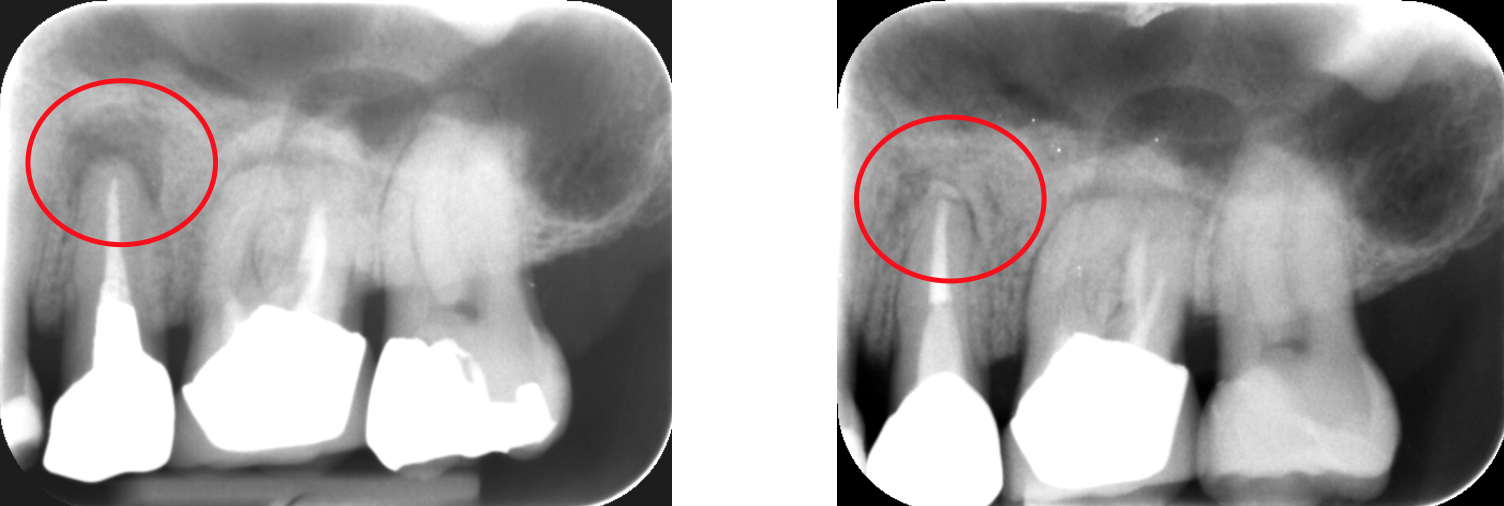

通常の根管治療を行っても症状が良くならない場合には外科的根管治療が必要となってきます。

歯根の外側に感染が及んでいる場合、通常の根管治療では感染源を除去することができないため、感染部位周辺の歯肉から感染源に直接アプローチする必要があります。

感染部周辺の歯肉を切開し、歯根の先端の病変部分を露わにします。

歯槽骨に穴を開け歯の根本から根管治療を行い、感染源を除去します

感染源を除去した後、感染している歯根の先端も取り除きます。

詰物をして歯槽骨の回復を待ち、切開部を縫合して完了です。